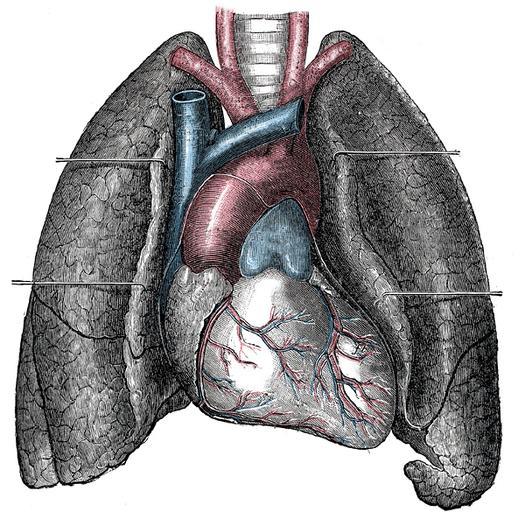

| View Original: | Gray490blanco.png (600x585) | |||

| Keywords: Gray490blanco.png es Vista anterior del corazón y pulmón en Front view of heart and lungs Other fields 1 Information field Ucfirst Plate 490 before 1858 Henry Gray Anatomy of the Human Body See Book section below 490 image without text Luisjchr Gray490 png Creator Henry Vandyke Carter Book Gray's Anatomy Gray's Anatomy plates Pd-old-100-1923 Heart organ | ||||